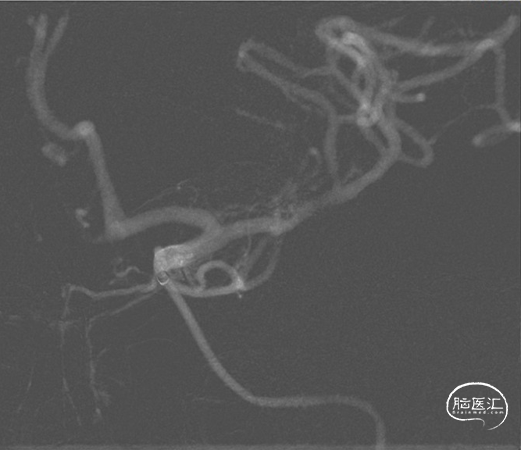

CTA

DSA

1、急性脑梗死。2、左侧大脑中动脉M1段闭塞。

ICAS合并血栓?

夹层合并血栓?

栓塞?